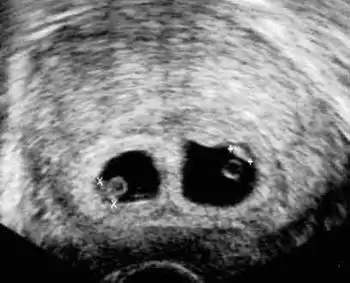

С появлением ультразвука врачи научились "устанавливать" количество детей в утробе мамы на самых ранних сроках. Перед вами - классическая двойня...

А это - четверня...